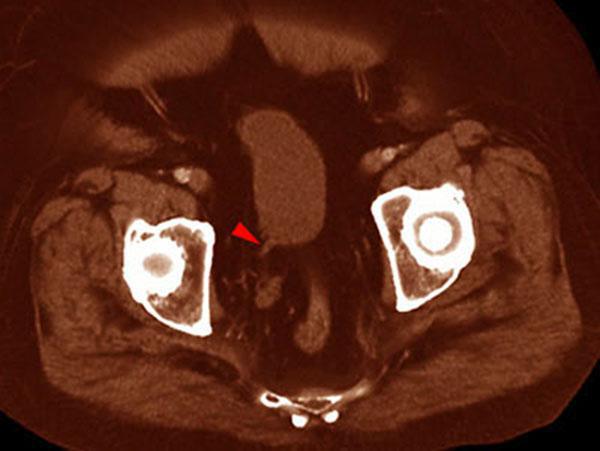

VR seccional. Visión axial caudal. Se observa la presencia de un único uréter derecho (punta de flecha) y una ausencia de la vesícula seminal izquierda